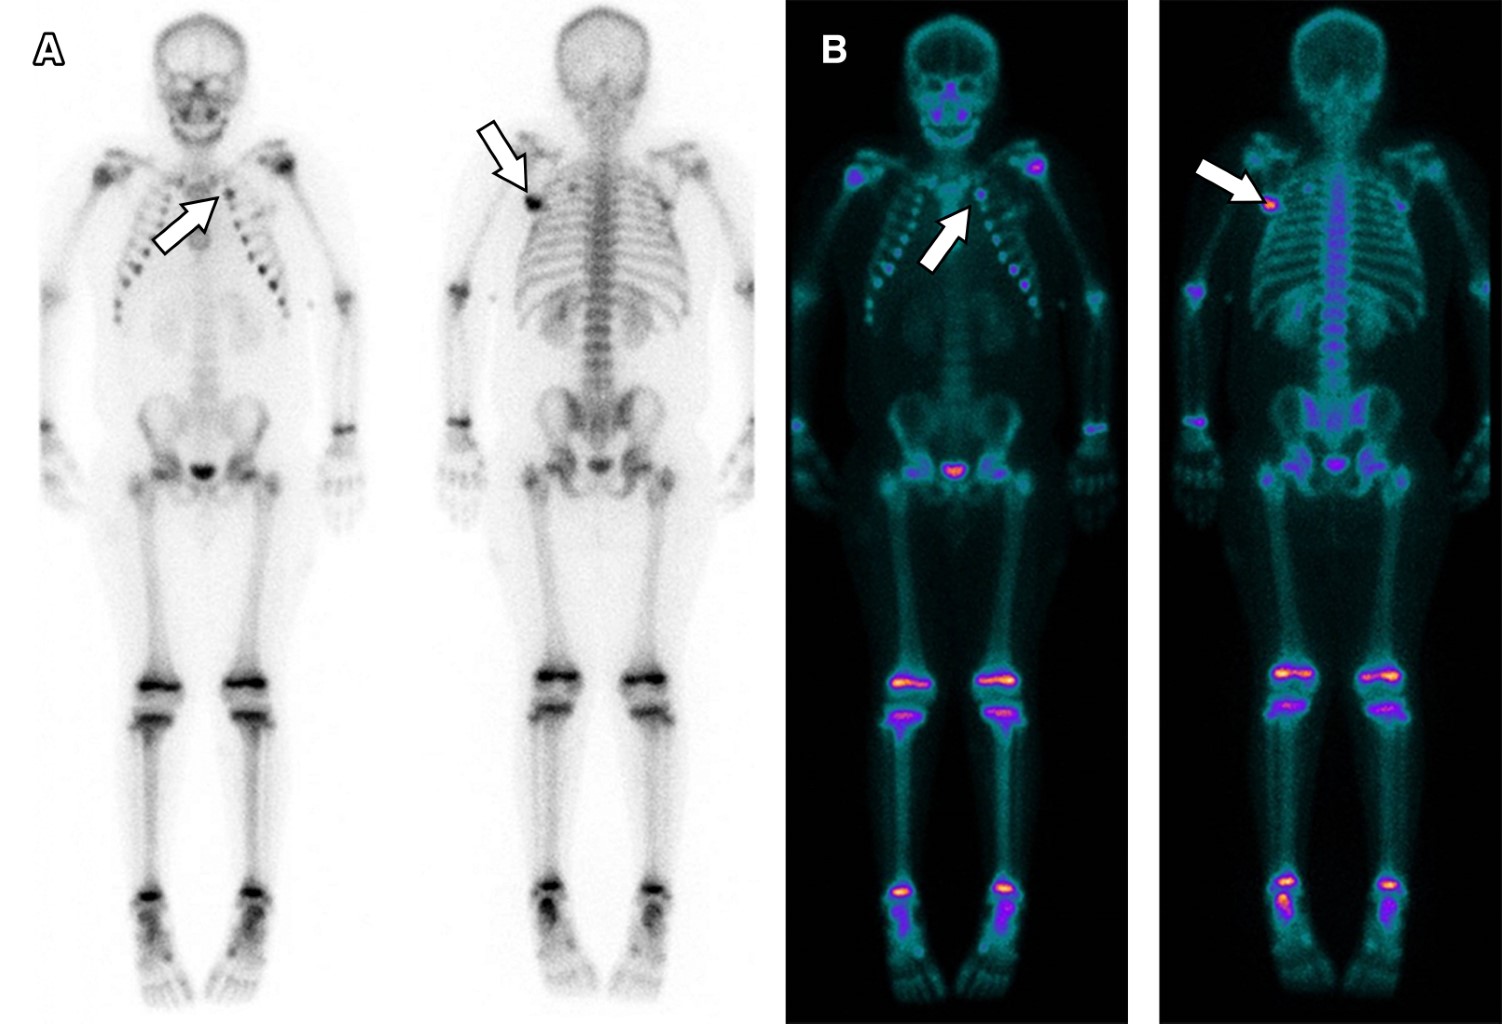

Reingresó a los siete días por neutropenia febril de alto riesgo, asociando nuevas lesiones similares a las descritas anteriormente. Se indicó PTZ, ciprofloxacina y TMS endovenoso. Por el mecanismo fisiopatológico de Aeromonas hydrophila se sospechó foco profundo productor de toxina que generaba lesiones secundarias en PPB. Se realizó gammagrafía ósea que mostró imágenes captantes en extremo anterior de la segunda costilla izquierda y ángulo escapular inferior izquierdo (Figura 2). Se completó con tomografía computada, la cual reportó lesiones líticas de bordes poco definidos y leve abombamiento de los planos blandos adyacentes, compatible con osteomielitis subaguda-crónica (Figura 3). Se realizó toilette y biopsia quirúrgica compatible con osteomielitis crónica, con cultivos negativos. Siete meses después se encuentra cumpliendo antibioterapia prolongada, sin nueva infección por dicha bacteria.

Osteomielitis. La osteomielitis por A. hydrophila raramente se ha reportado como sitio de infección extraintestinal.3-5 Ante la sospecha clínica, es indispensable la realización de radiografías y, cuando son negativas, está indicada la gammagrafía ósea.4